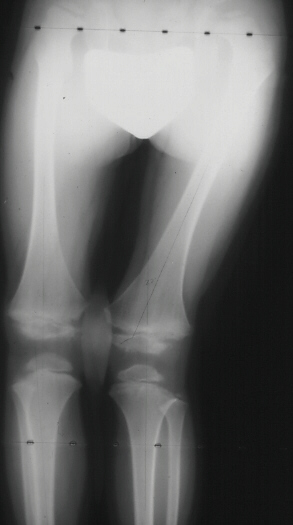

- Limb epiphyses show delayed appearing centers of ossification, often

demonstrating a fragmented appearence. Joint involvement is usually symmetric.

- Premature arthrosis of weight-bearing joints, most frequently the hips,

due to delay in ossification of the capital femoral epiphysis. The cartilaginous

femoral head model becomes misshapen and incongruous with time, leading

to early arthritis.

- Must differentiate M.E.D. from Perthes' disease. M.E.D. is usually

symmetric, does not show the radiographic changes characteristic of Perthes'

over time, not associated with metaphyseal cyst formation. and the acetabulum

is often irregular unlike Perthes'.